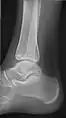

- مچ (قوزک) پا - AP و جانبی

مچ پا قدامی

چرخش داخلی ۱۵ درجه جانبی

جانبی (کمی کم کیفیت با دیدن مستقیم از طریق مفصل مچ پا)

صفحه جانبی مایل (برای تجسم مرز خلفی تیبیا)